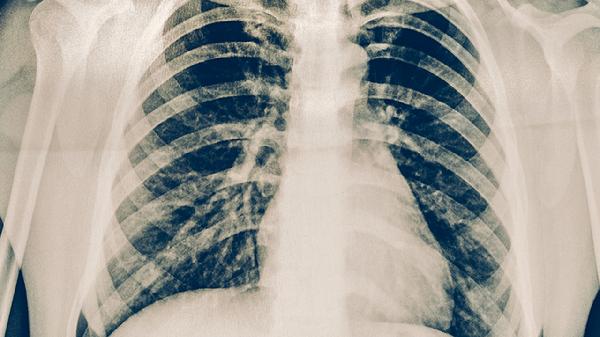

肺癌患者使用中药需严格遵循辨证论治原则,避免自行用药。治疗期间应保持均衡饮食,适量补充优质蛋白和维生素,避免辛辣刺激性食物。建议进行适度有氧运动如散步、太极拳,但需避免过度劳累。定期复查胸部CT、肿瘤标志物等指标,配合医生调整治疗方案。出现咯血、持续胸痛等症状时应立即就医。